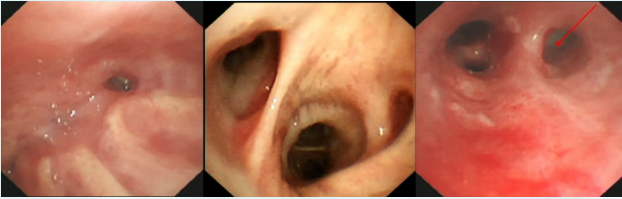

5月11日行气管镜右中叶支气管内活瓣置入术(EBV-TS 5.5)5

图片

5  右中叶支气管内活瓣置入术(2023-05-11)